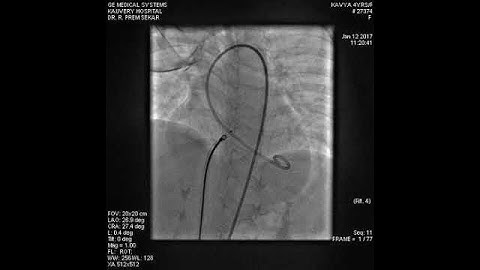

Proximal Disc of symmetrical PMVSDO deployed across the perimembranous VSD